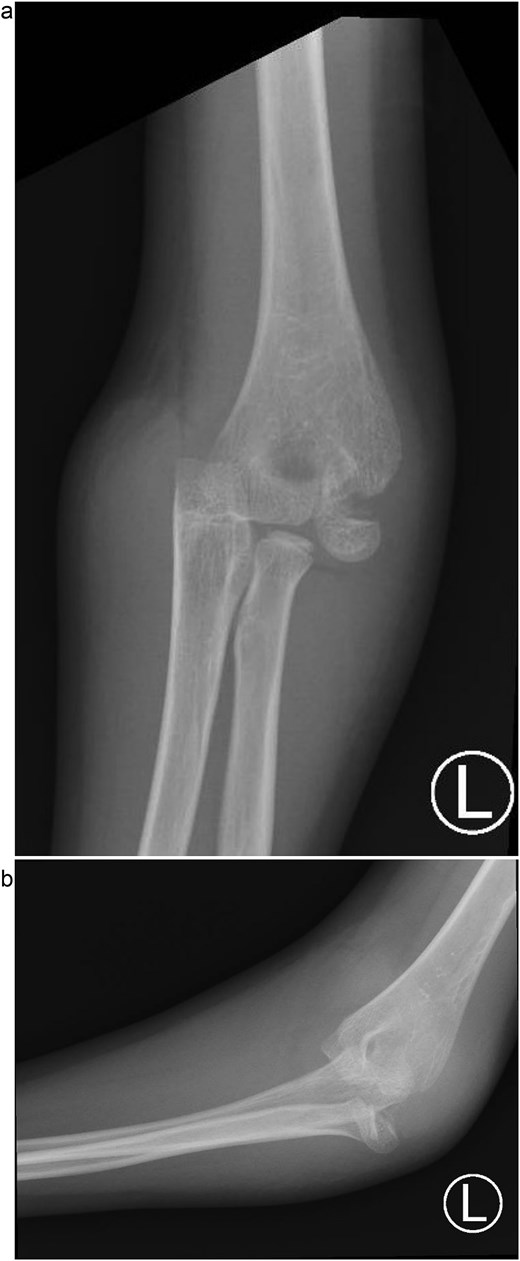

An 8-year-old boy presented to the emergency department with severe left elbow pain and deformity after falling while playing football. He reported landing on his arm but could not recall the exact elbow position. Examination showed significant swelling, deformity, and lateral elbow tenderness. The skin was intact, distal pulses and capillary refill were normal, and neurological assessment confirmed intact radial, ulnar, median, and anterior interosseous nerve function. Radiographs in anteroposterior and lateral views, along with a 3D CT scan, demonstrated a posteromedial dislocation of the elbow associated with a displaced fracture of the lateral condyle of the humerus (Fig. 1a).

(a) Pre-reduction anteroposterior radiograph of the left elbow showing posteromedial dislocation of the ulnohumeral joint with displaced lateral humeral condyle fracture. (b) Lateral radiograph demonstrating posterior displacement of the olecranon and lateral condyle fragment.